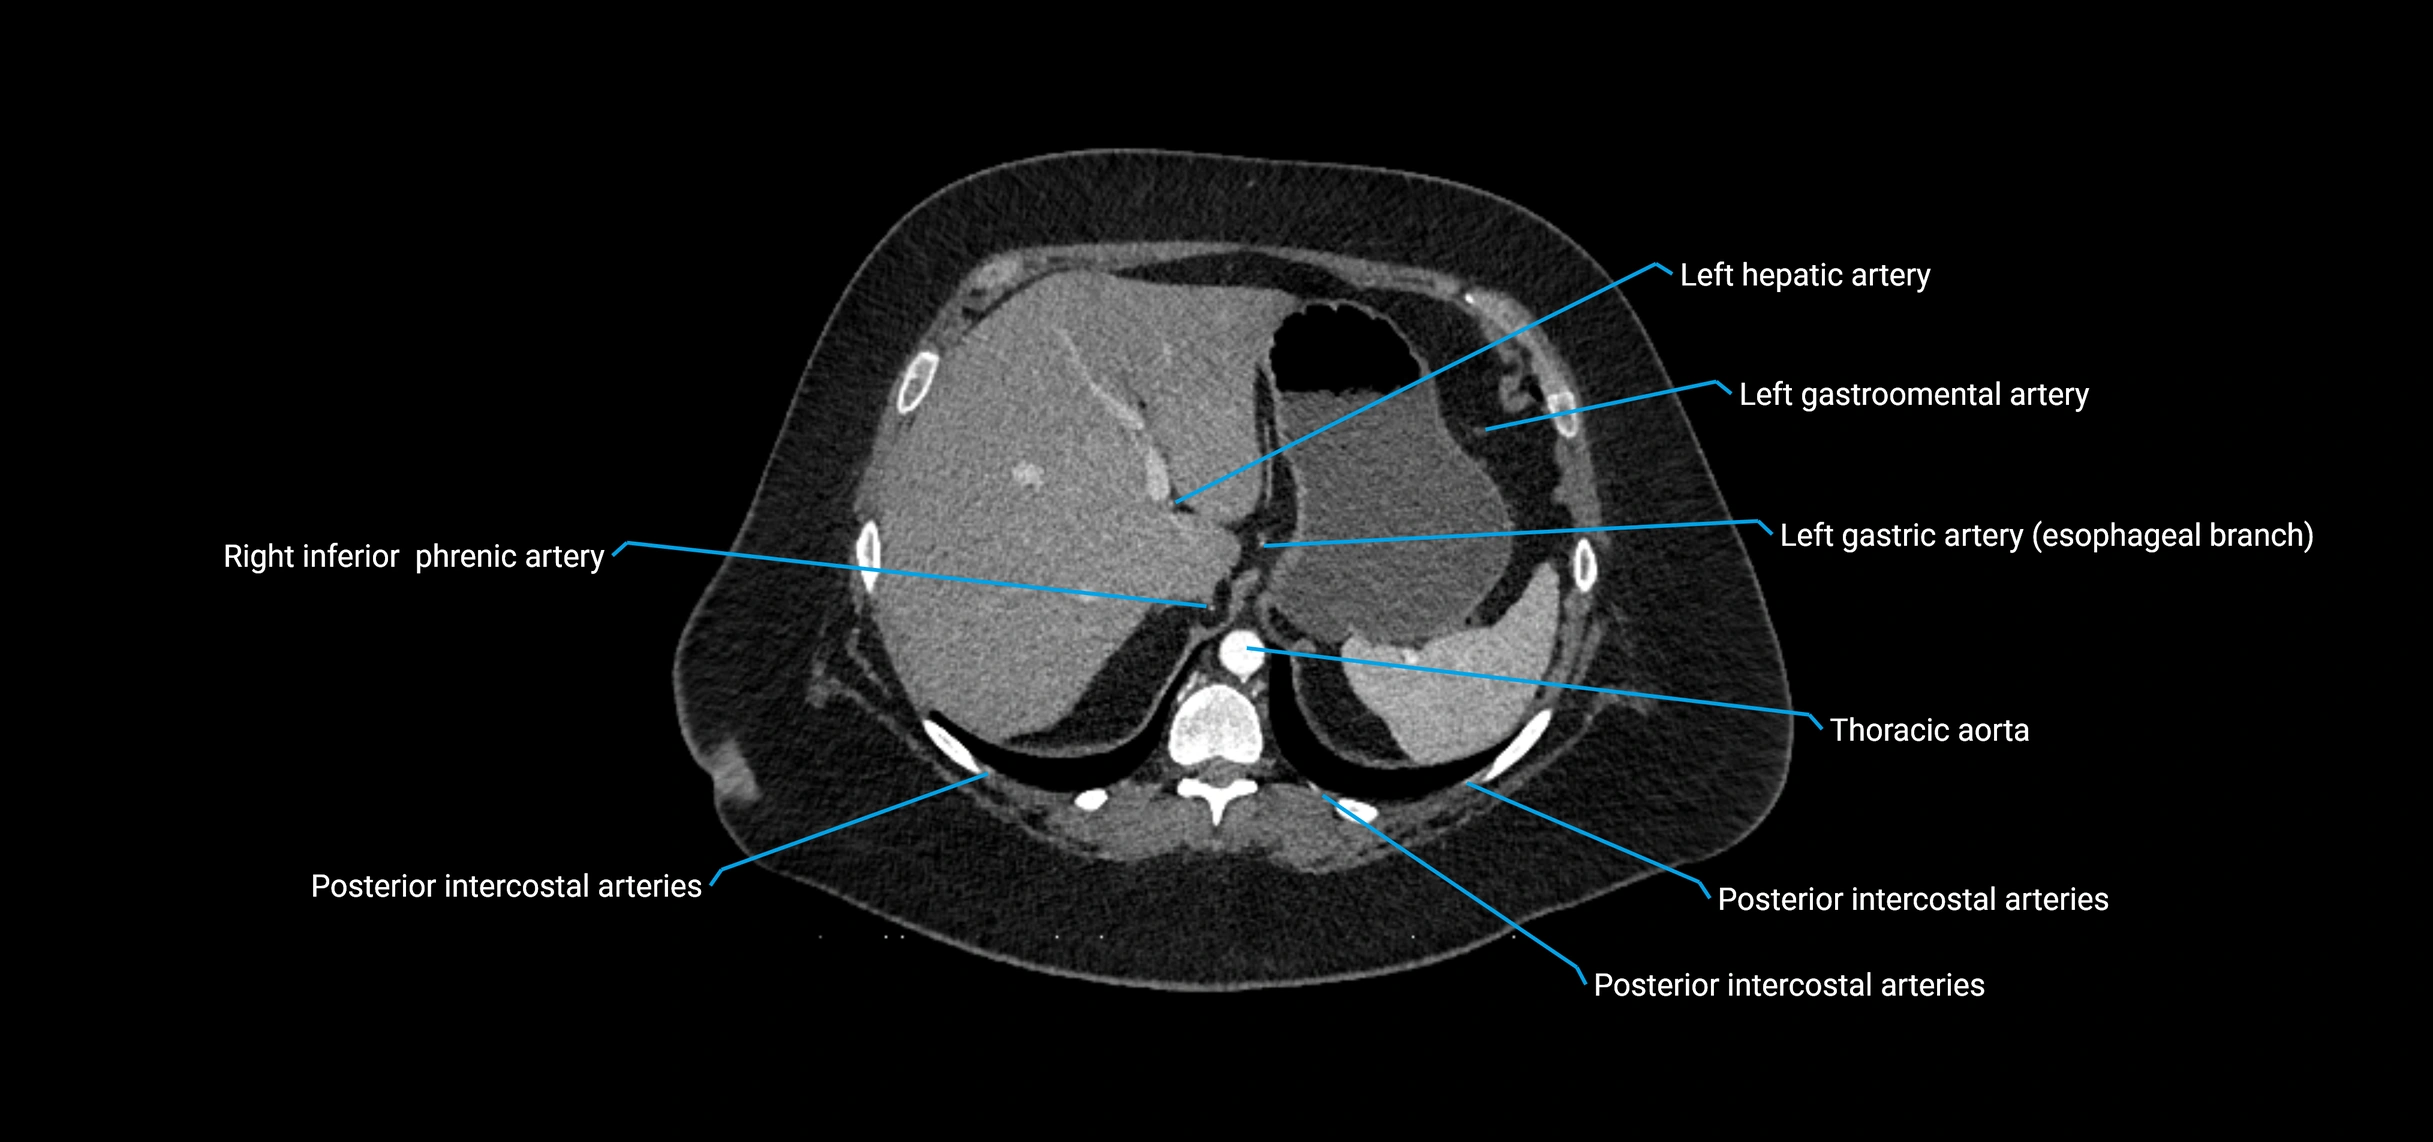

CT Appearance

Non-contrast CT:

• Appears as a tubular soft tissue structure anterior to vertebral bodies

• Calcified atherosclerotic plaques appear as hyperdense foci along the wall

• Useful for screening abdominal aortic aneurysm (AAA) size and mural calcification

Contrast-enhanced CT (CTA):

• Gold standard for abdominal aortic imaging

• Provides excellent detail of lumen, wall, aneurysm, thrombus, and branch vessels

• Multiplanar and 3D reconstructions help in aneurysm measurement, stent graft planning, and dissection evaluation

• Detects acute rupture, traumatic injury, or occlusion with high sensitivity

CT images

image